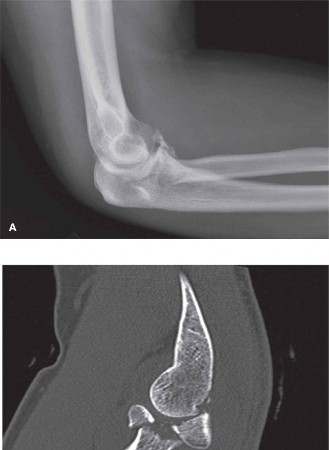

A 43-year-old male presents to the emergency department after falling approximately 15 ft while trimming tree…